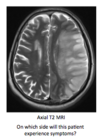

Label the image

T2 weighted MRI:

What is the appearance of bone?

What is the appearance of CSF?

On a T2 weighted MRI bone will appear black and CSF will appear white.

Note also that cerebral grey matter can be distinguished from white matter tracts on a T2 weighted MRI.